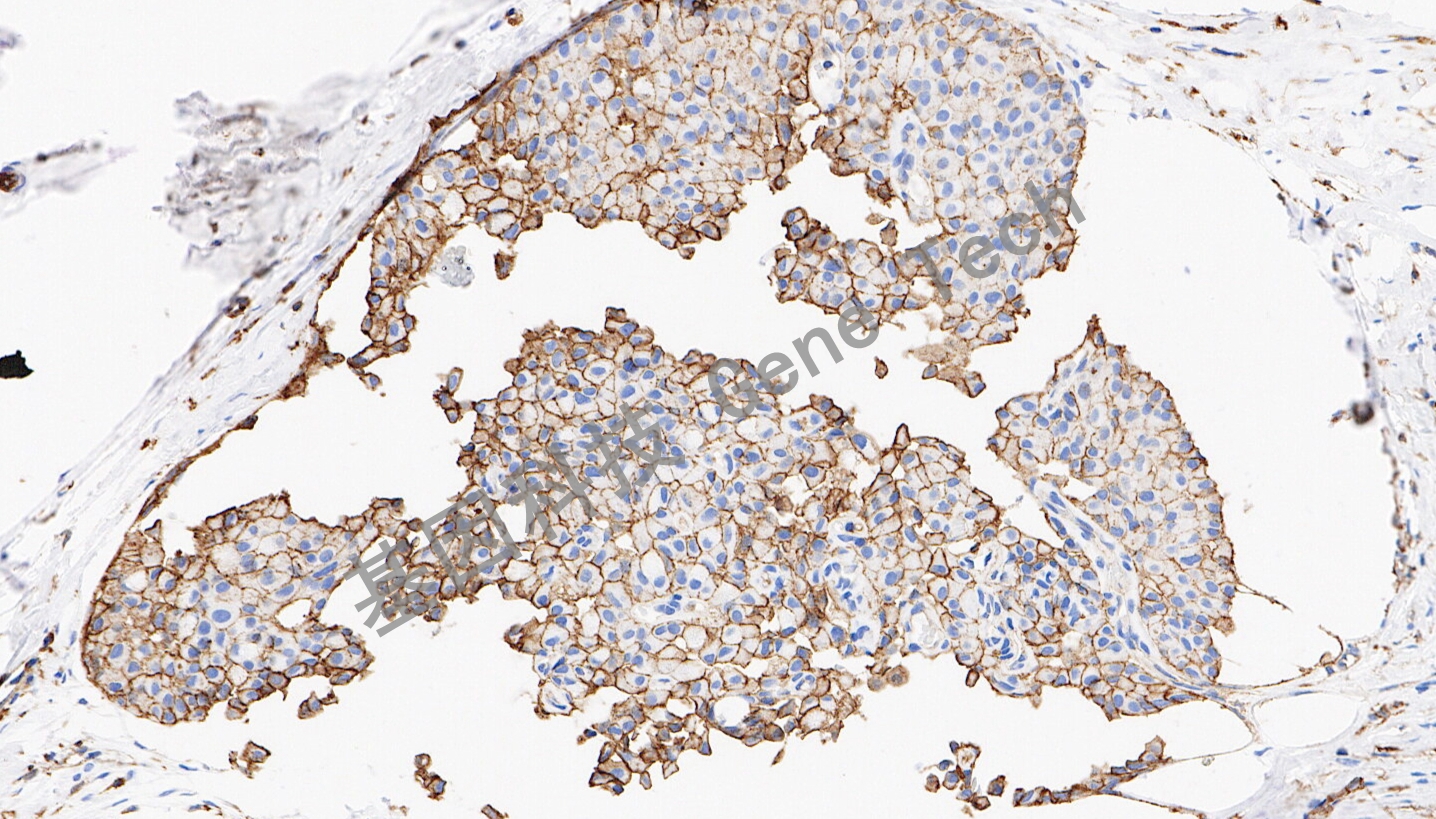

JAM-A 兔抗人 連接黏附分子A(JAM-A)抗體試劑(免疫組織化學(xué)法)

| 預(yù)處理:高pH熱修復(fù) | 陽(yáng)性部位:細(xì)胞膜 | 陽(yáng)性對(duì)照:乳腺癌 |

| 簡(jiǎn)介:連接粘附分子A(JAM-A)也被稱(chēng)為JAM-1,是位于上皮細(xì)胞和內(nèi)皮細(xì)胞間緊密連接處的一種跨膜糖蛋白,屬于免疫球蛋白超家族。JAM-A調(diào)節(jié)多種細(xì)胞過(guò)程,包括緊密連接組裝、上皮-間充質(zhì)轉(zhuǎn)化(EMT)、白細(xì)胞遷移、病毒結(jié)合、血小板活化和血管生成。JAM-A通過(guò)緊密連接的啟動(dòng)引起同型細(xì)胞間的黏附,與腫瘤黏附、浸潤(rùn)和轉(zhuǎn)移密切相關(guān)。研究表明,JAM-A在乳腺癌患者腫瘤標(biāo)本呈異常高表達(dá),并提示預(yù)后不良。 | ||

| 乳腺癌石蠟切片,用 JAM-A (GT2598)染色,細(xì)胞膜陽(yáng)性,DAB 顯色。 | ||